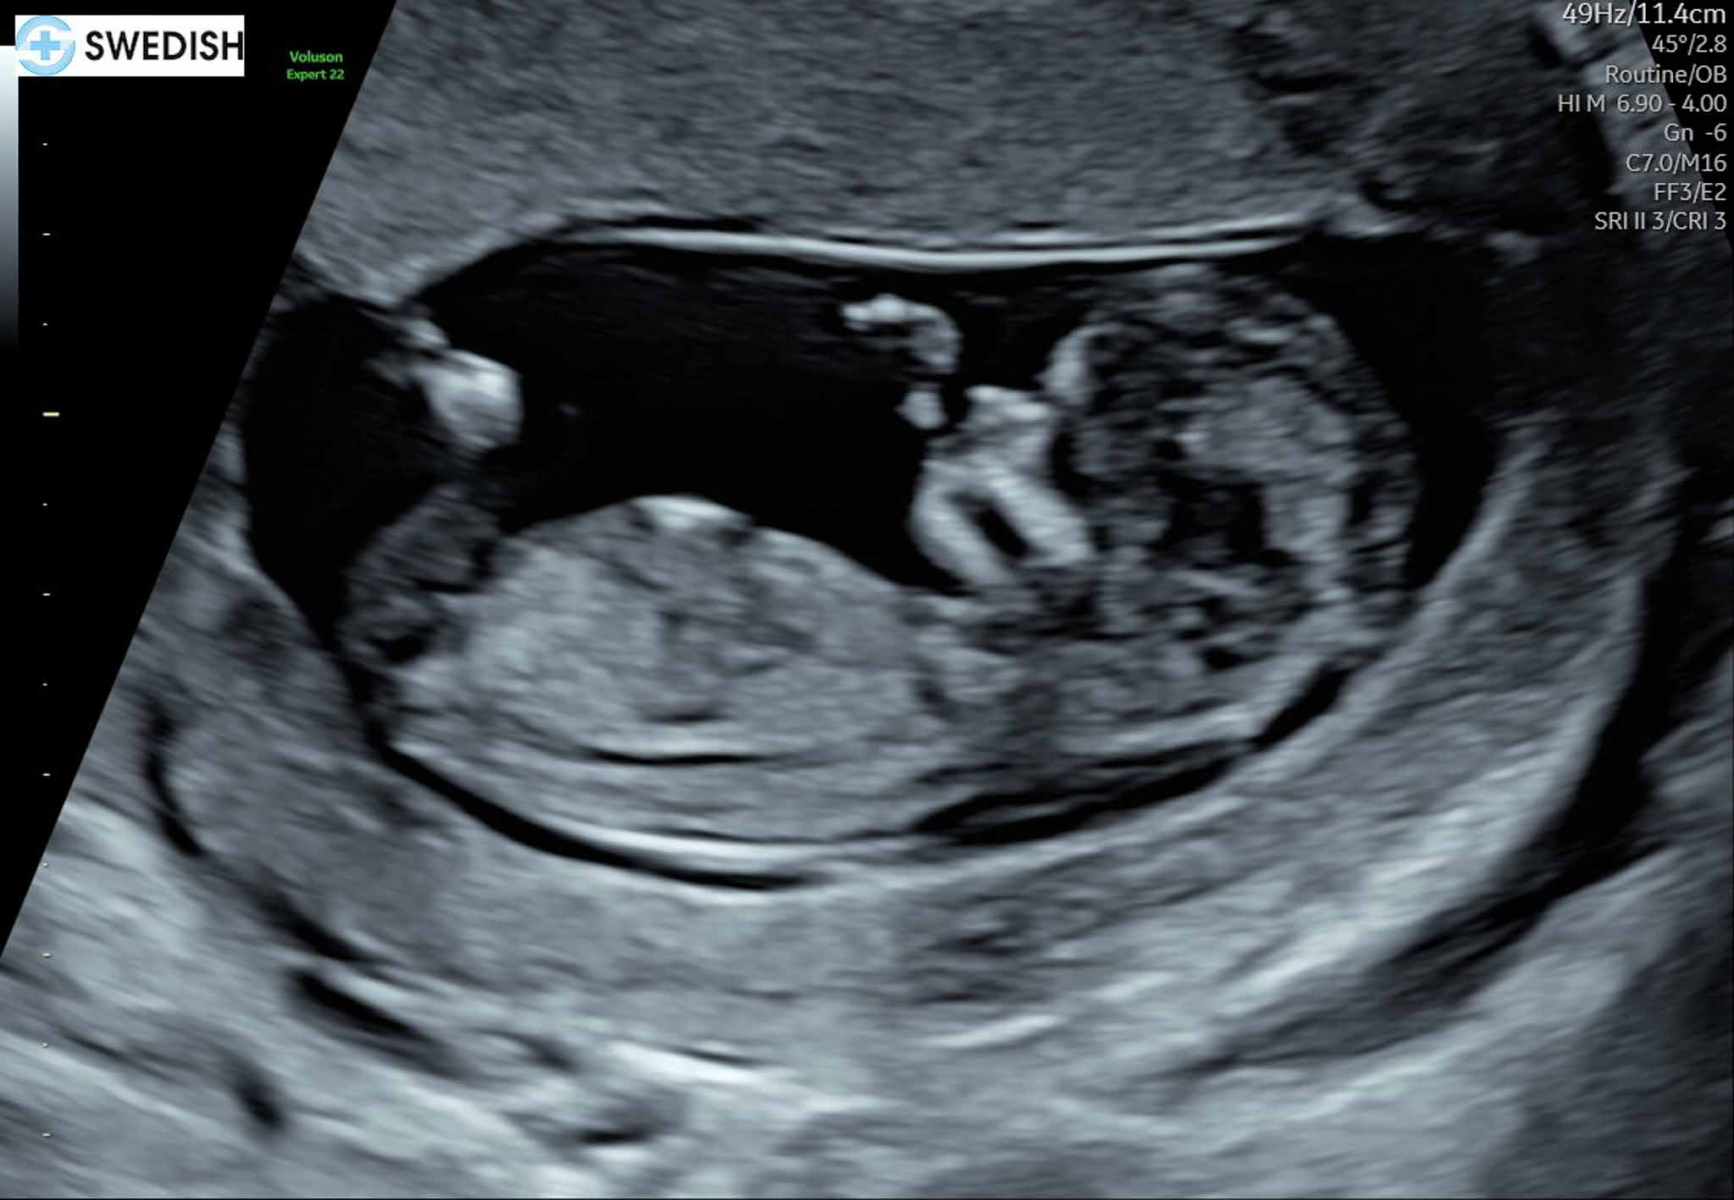

Two weeks later, on Sunday, April 27, I took a pregnancy test expecting it to be negative. Our doctor had said we could resume egg retrievals once my next period started, so I just wanted to close out the last cycle.

After dipping the stick, I saw the first line appear and looked away, expecting the usual negative result. I didn’t think much of it—there’s always a single control line. But when I glanced back seconds later, I saw a second line. I didn’t realize the first line indicated a positive result—the second was the control line. Wait… Two lines means pregnant, right? I was in total shock. My mind went blank. Could this be real? Did I just get pregnant naturally?

I thought about keeping it a secret to surprise Chi in a more special way, but I couldn’t hold it in. I walked into the dining room holding the test with a shocked but smiling face. He had no idea I took a pregnancy test. “Uh… I think I’m pregnant,” I said. He looked confused, so I showed him the test. “Two lines means pregnant.”

He couldn’t believe it and thought I was joking or imagining things. He said I looked like I’d just won the lottery, which is exactly how I felt. I needed confirmation, so I drank more water and took more tests. All positive —I was pregnant!

In actuality, this isn’t the ending I expected to write. I had imagined a bittersweet goodbye to the idea of a second child, but instead, I’m writing with a full heart. Against all odds, we got pregnant naturally and were blessed with a miracle—not once but twice—something I never thought possible.